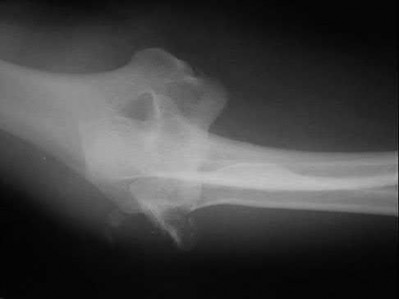

A 24-year-old woman is thrown from her motorcycle and sustains the closed injury shown in Figures A through C. Open reduction and internal fixation is planned. What surgical technique will best allow visualization of the joint surface and allow early range of motion?

Access to complex intra-articular fractures is best achieved by an olecranon osteotomy (OO). Fixation can be with parallel plating or orthogonal plating.

Bicolumnar fixation of distal humerus fractures should follow the principles outlined by O'Driscoll: Distal fragments should be held by as many screws as possible; every screw in the distal fragments should pass through a plate; each screw should engage as many articular fragments as possible.

Galano et al. review treatment for bicolumnar distal humerus fractures. They note that the olecranon osteotomy, Alonso-Llames triceps sparing and Campbell triceps splitting approaches expose 57%, 46% and 35% of the articular surface, respectively. The OO and paratricipital (triceps sparing)

approaches allow for early ROM. Protected motion is required for the O'Driscoll TRAP and Bryan-Morrey approaches for tendon-to-bone healing.

Coles et al. retrospectively reviewed the OO in fixation of 70 fractures. Osteotomy fixation was with an intramedullary screw and dorsal ulnar wiring, or with a plate. The rate of OO increased with fracture difficulty (from AO type C1-C3). There was 1 delayed union but no nonunions.

Figures A and B show a AO/OTA type C2 intraarticular distal humerus fracture. Figure C is a coronal CT scan showing intraarticular comminution. Illustration A shows fixation of the fracture with bicolumnar plating through an olecranon osteotomy approach. Illustration B shows the various approaches to the distal humerus (left, Campbell triceps splitting; center left, O'Driscoll triceps reflecting anconeus pedicle; center right, Bryan-Morrey approach, leaving the triceps attached laterally to the fasciocutaneous flap, but elevating it off the ulna; right, olecranon osteotomy). Illustration C shows 3 methods of olecranon osteotomy (A and B, Intra-articular transverse; C-F, Extra-articular oblique; G, Intra-articular chevron).